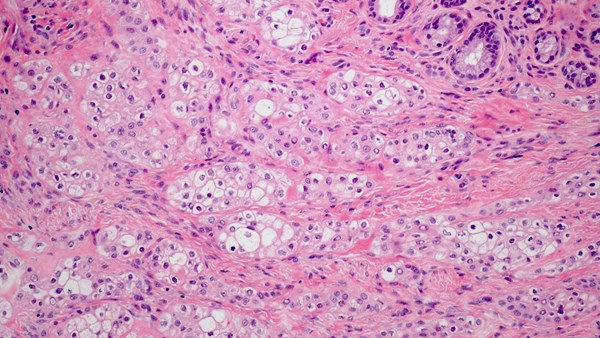

Salivary Gland Cancers

These are a rare group of cancers. They represent less than 5% of all head and neck malignancies and can also present in other areas of the body, including the windpipe, breast, skin and the vulva. Surgery, where possible, followed by radiotherapy is the most common treatment. Supporting research and clinical trials is vital to improve survival and reduce side effects in all patients.